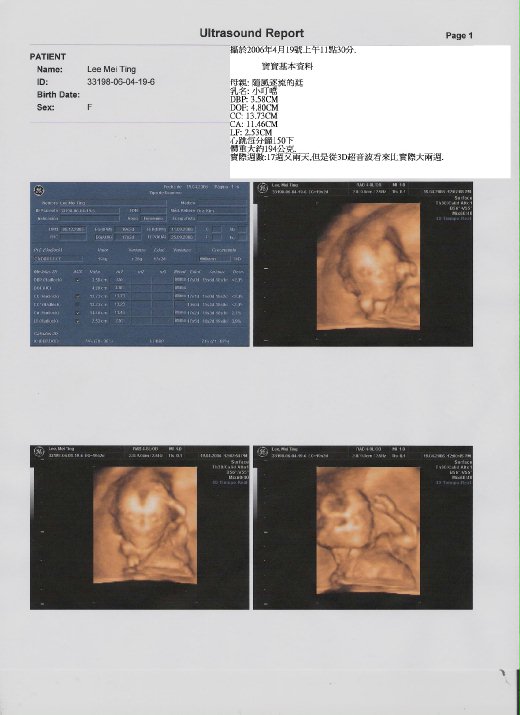

以下是寶寶基本資料

母親: 隨風逐流的廷

乳名: 小叮噹

週數: 17週又兩天,可是醫生說看起來比實際大兩週.

體重: 194公克左右.

心跳: 每分鐘150下.